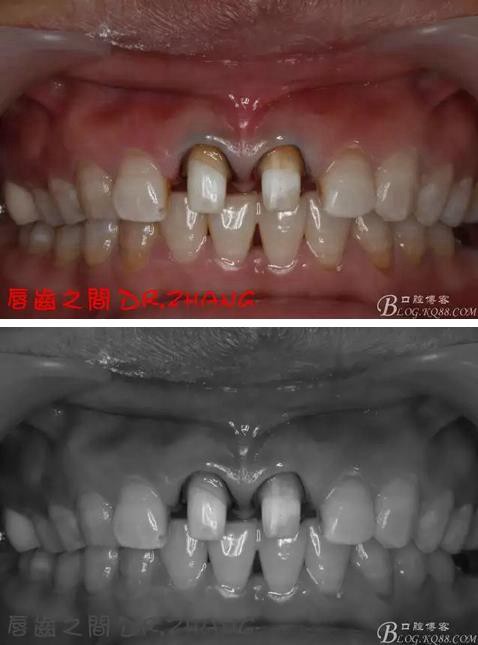

牙體預(yù)備后 硅橡膠取模 臨時牙恢復(fù)形態(tài)

復(fù)診:臨時牙良好 患者自訴無不適癥狀 去除臨時修復(fù)體 排齦 清理牙面 試戴全瓷修復(fù)體后粘結(jié) 常規(guī)醫(yī)囑 不適隨診

總結(jié):沒有術(shù)前照片 預(yù)備牙體過長 顏色還是有差距